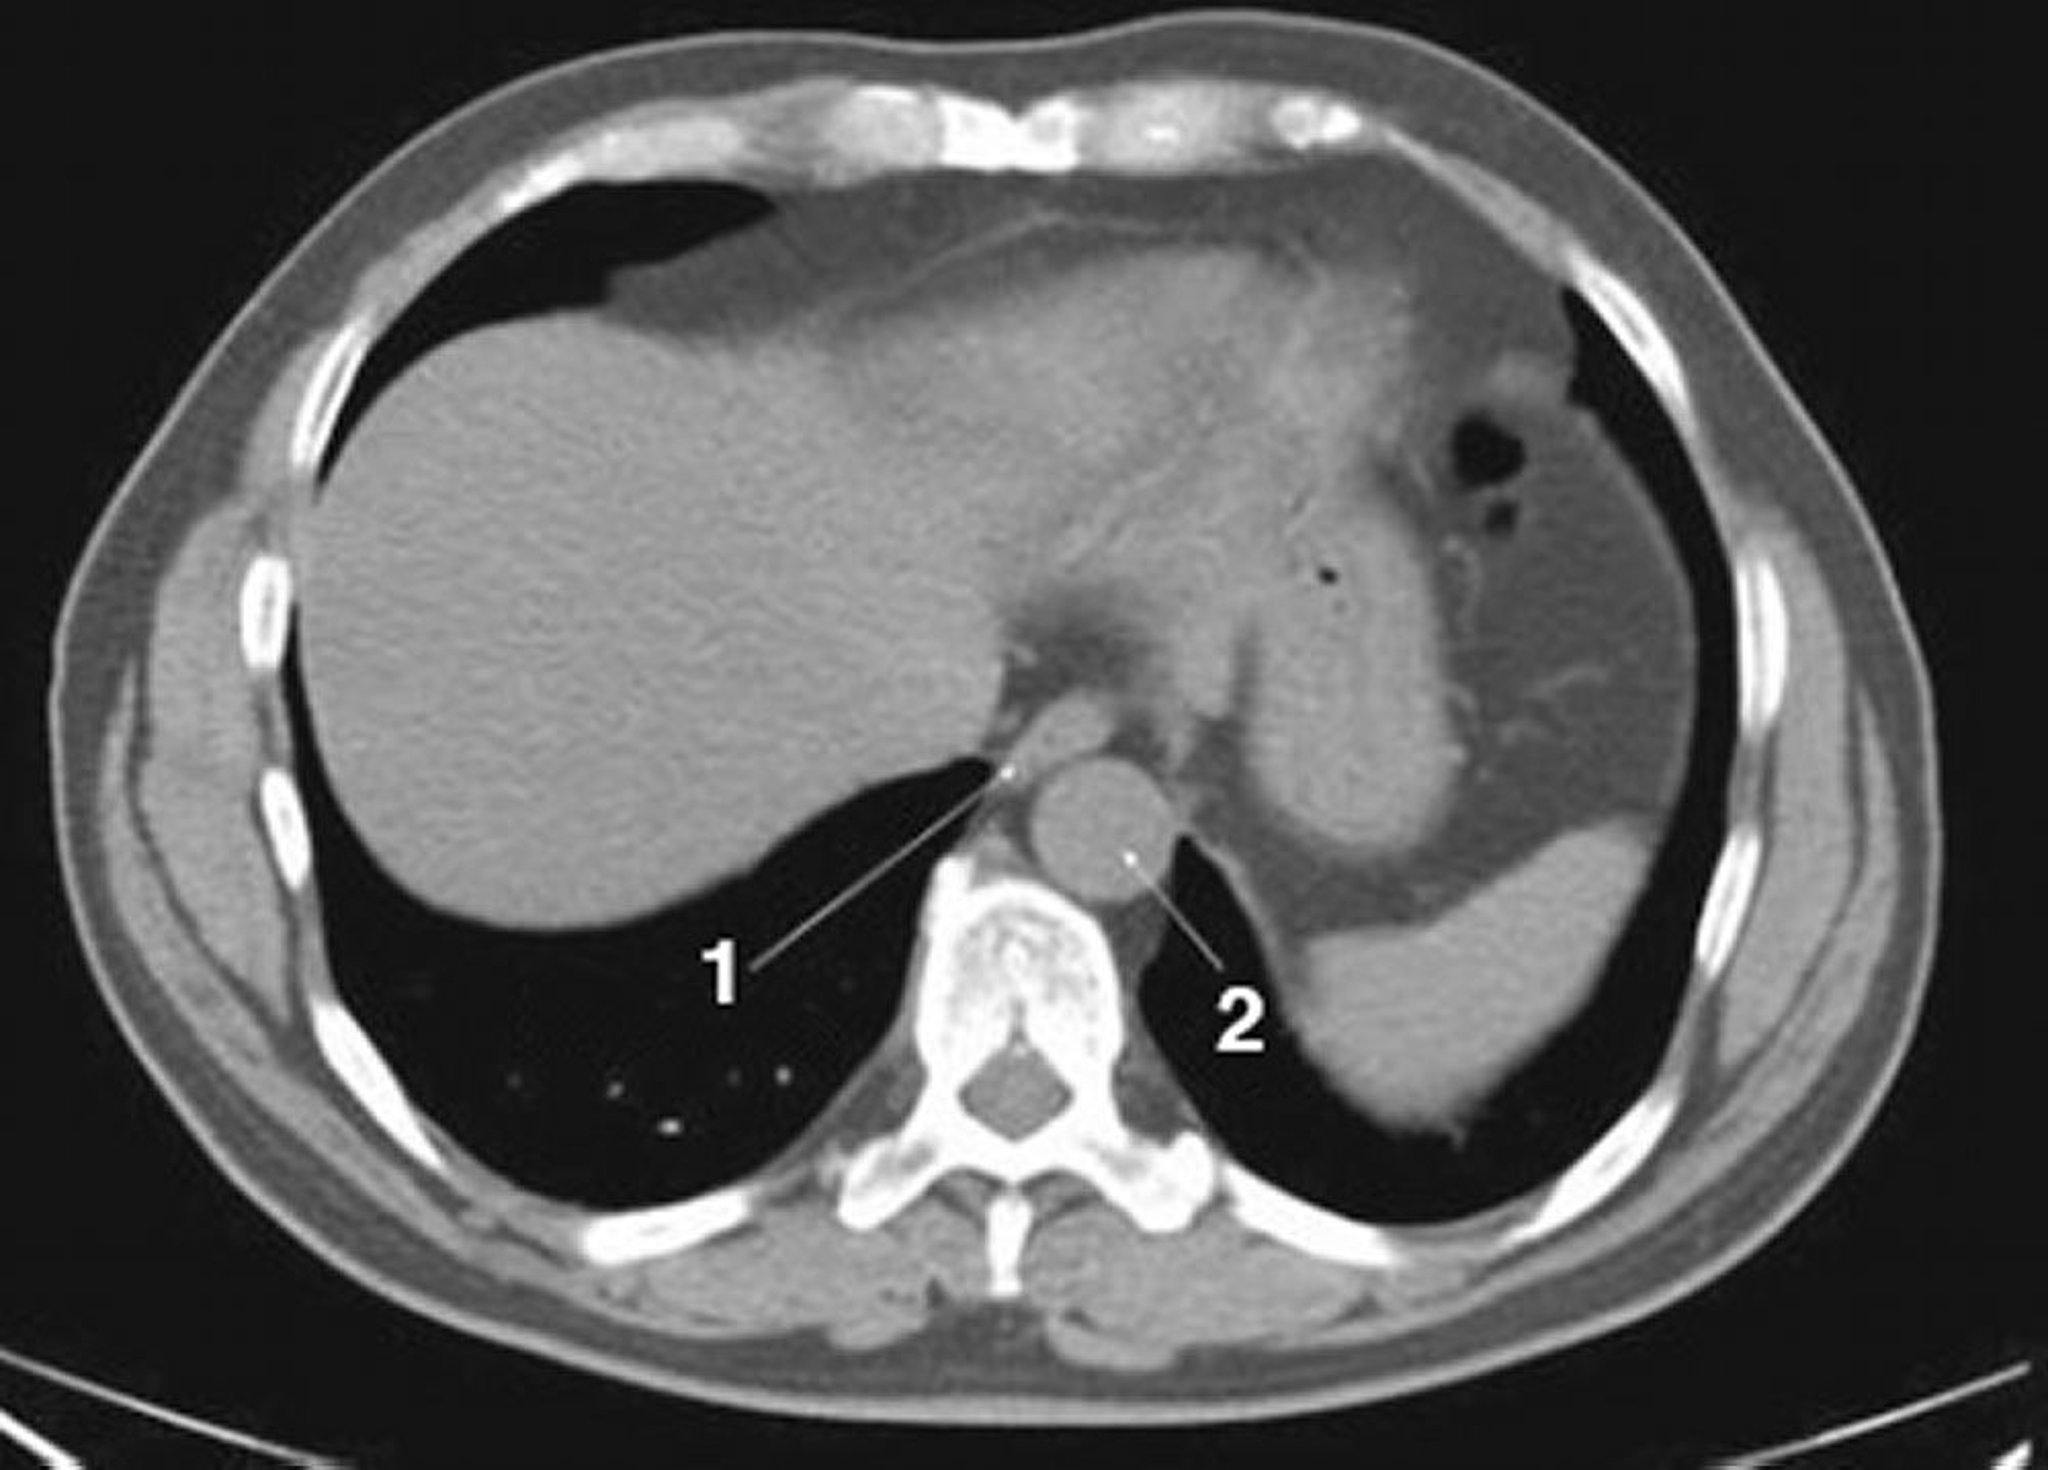

CT-Scan von Abdomen und Becken mit normaler Anatomie ohne Kontrastmittel (Folie 1)

1 = Ösophagus; 2 = Aorta.